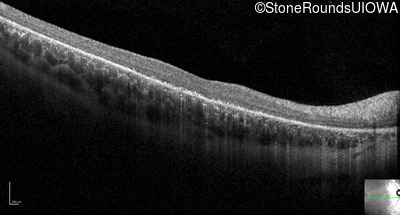

Optical Coherence Tomography - Right - 5/100 sc

Exemplar / OCT Stack